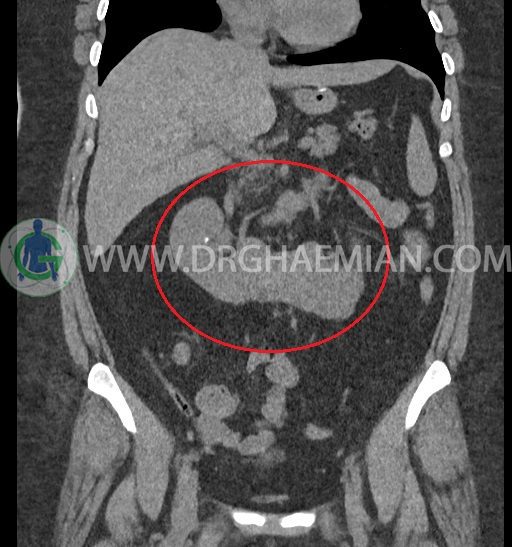

سی تی اسکن شکم و لگن با استفاده از اشعات ایکس تصاویر عرضی از ناحیه شکم و لگن ایجاد میکند. در این کیس کلیه نعل اسبی و سنگ کلیه مشاهده می شود.

در سی تی اسکن اسپیرال شکم و لگن بدون کنتراست (مولتی دیدکتور 16 با مقاطع ظریف و بازسازی های ساژیتال و کرونال) :

-horseshoe kidney

-حداقل سه سنگ 5mm در کلیه راست و یک سنگ 3mm در کلیه چپ بدون شواهدی از هیدرونفروز